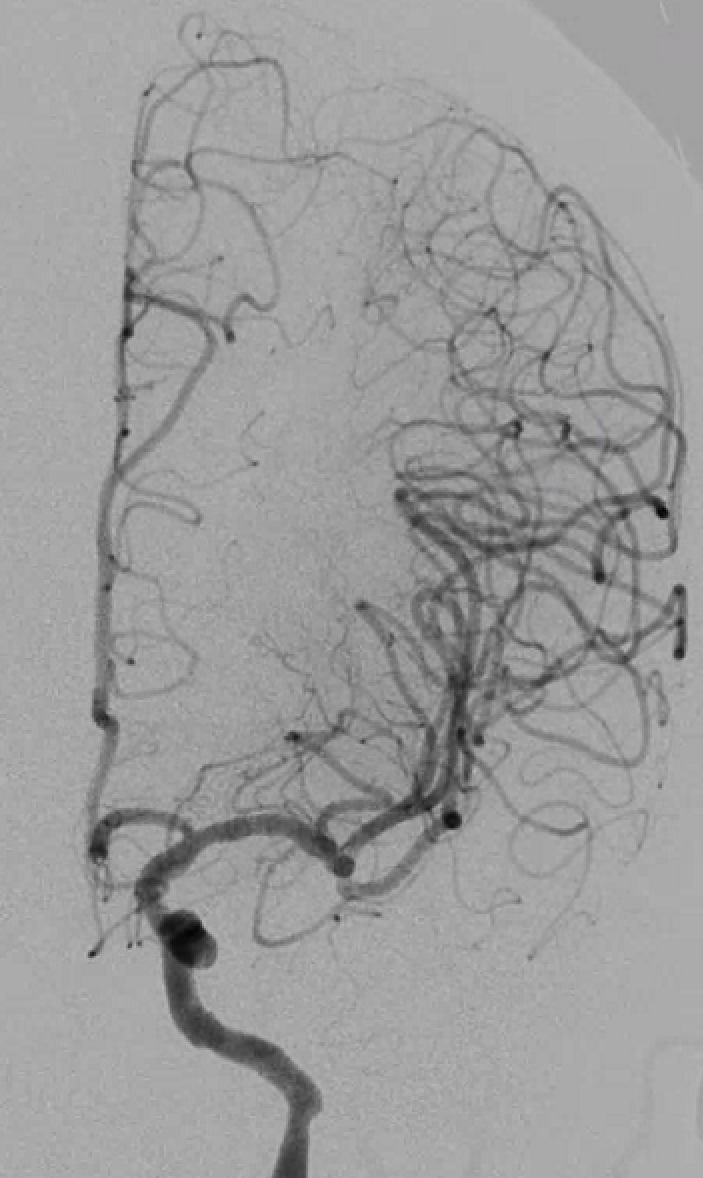

脑血管造影提示右侧颈内动脉颅内段多发动脉瘤(反主动脉弓)

脑血管造影提示右侧颈内动脉颅内段多发动脉瘤

4mm×30mm Streamline

术后4月余随访:多发动脉瘤均未见显影,远端残余轻度狭窄

术前术后对比